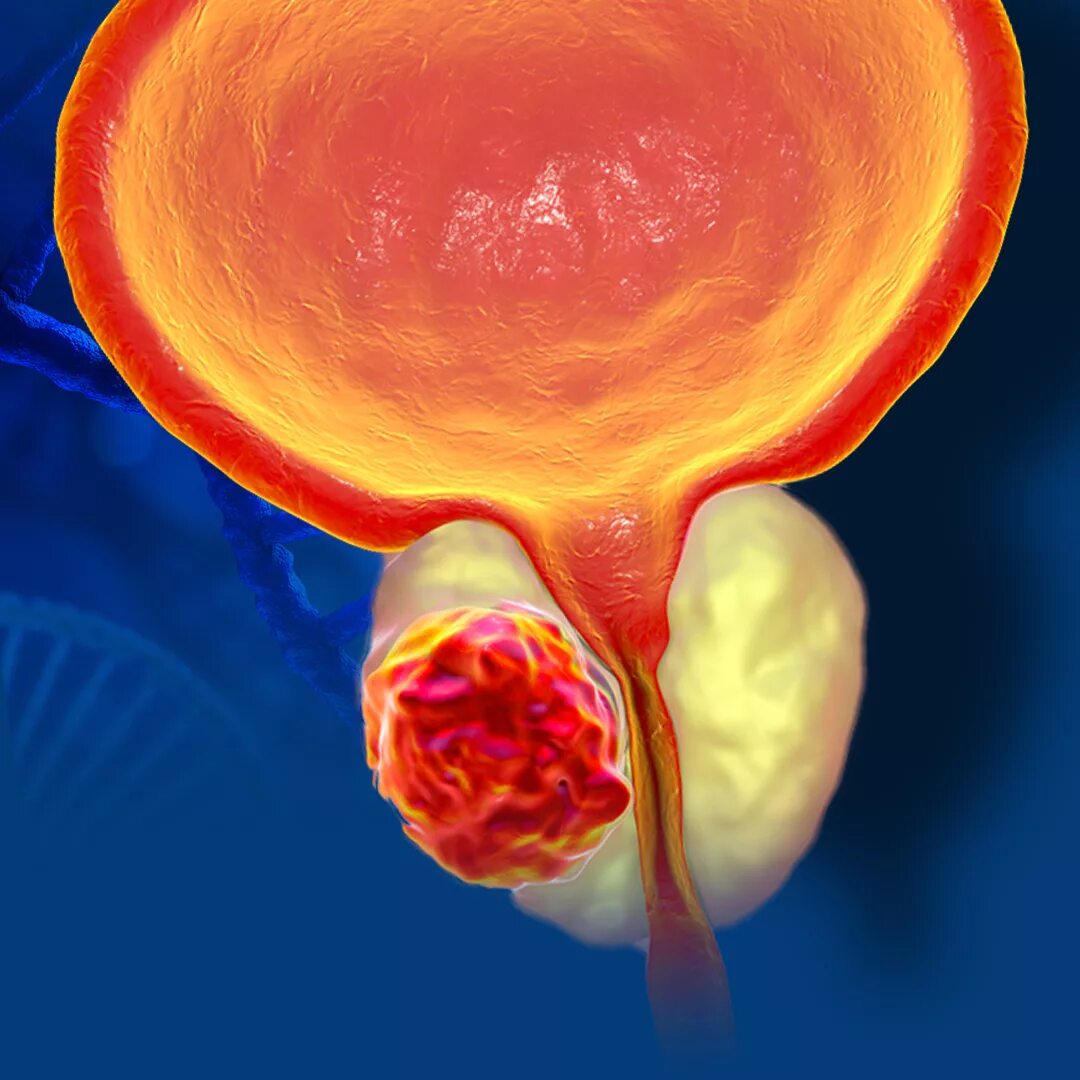

Опухоль аденомы простаты симптомы. Раковые заболевания простаты. Раковая опухоль простаты. Предстательная железа у мужчин онкология

Опухоль аденомы простаты симптомы. Раковые заболевания простаты. Раковая опухоль простаты. Предстательная железа у мужчин онкология Злокачественная опухоль простаты. Злокачественное новообразование предстательной железы. Злокачественные новообразования простаты

Злокачественная опухоль простаты. Злокачественное новообразование предстательной железы. Злокачественные новообразования простаты Карцинома предстательной железы. Злокачественное новообразование предстательной железы. Cancer предстательной железы. Аденома предстательной железы – это опухоль

Карцинома предстательной железы. Злокачественное новообразование предстательной железы. Cancer предстательной железы. Аденома предстательной железы – это опухоль Предстательная железа, Prostata. Аденома предстательной железы. Карцинома предстательной железы. Злокачественное новообразование предстательной железы

Предстательная железа, Prostata. Аденома предстательной железы. Карцинома предстательной железы. Злокачественное новообразование предстательной железы Cancer предстательной железы. Аденокарцинома предстательной железы. Онкология предстательной железы

Cancer предстательной железы. Аденокарцинома предстательной железы. Онкология предстательной железы Опухоль предстательной железы у мужчин. Злокачественное новообразование предстательной железы. Эктопия предстательной железы. Карцинома предстательной железы

Опухоль предстательной железы у мужчин. Злокачественное новообразование предстательной железы. Эктопия предстательной железы. Карцинома предстательной железы